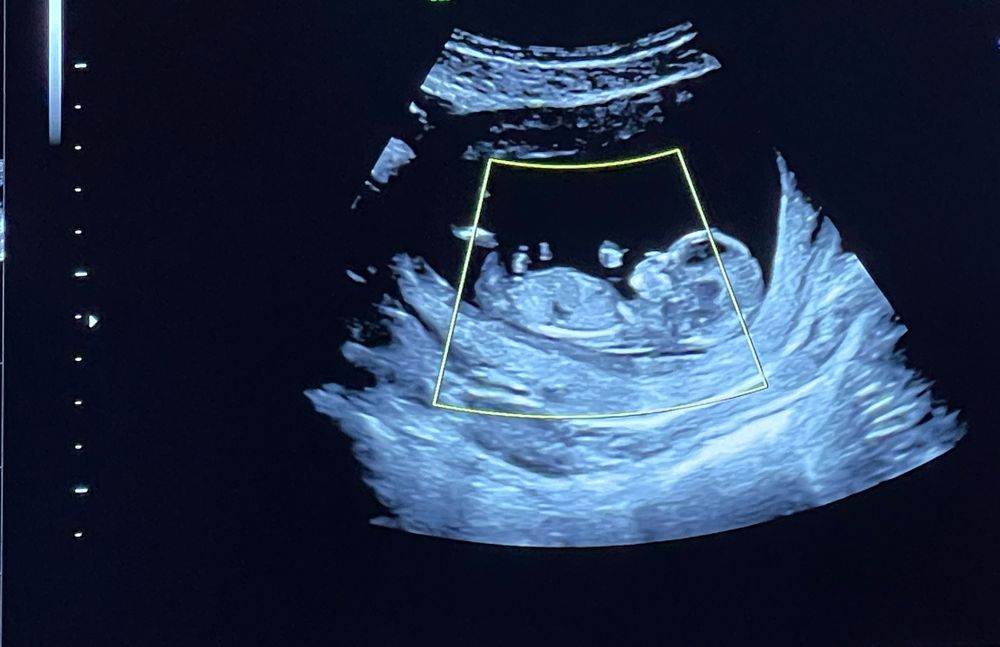

1 скрининг) кто же там 🙈

По 2 фото девочка)

Добрый день.  судя по углу наклона полового бугорка - высоко вероятно, что у Вас девочка.  удачи! 🥳